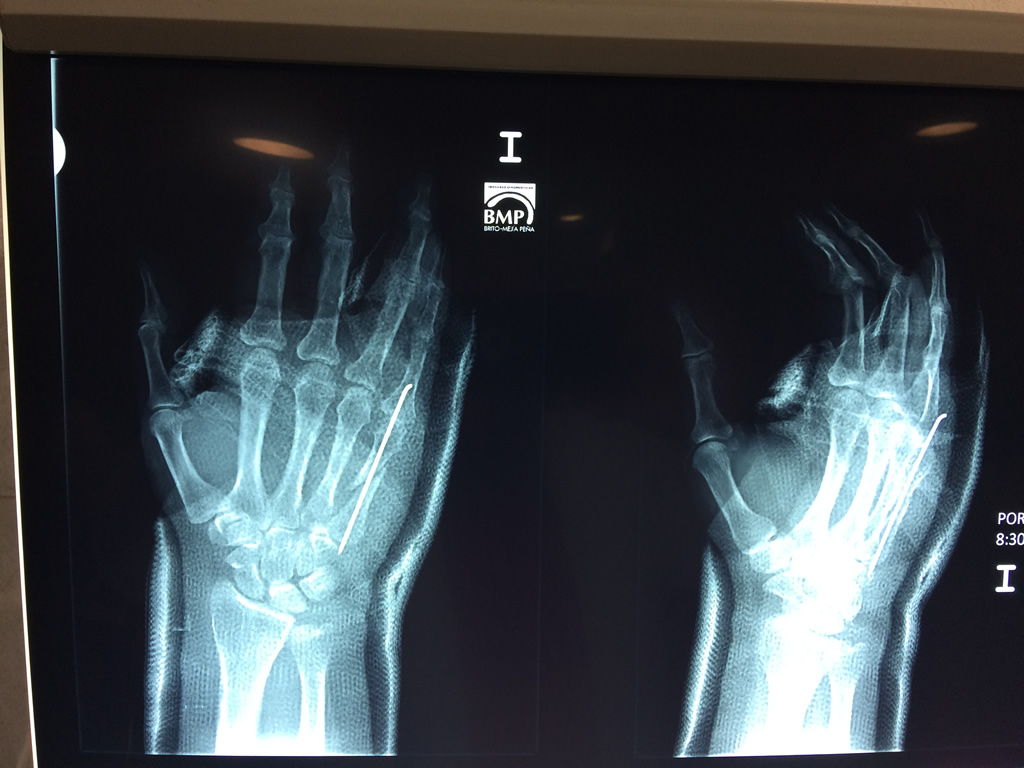

Los procedimientos más comunes en cirugía de la mano son aquellos destinados a reparar traumatismos, incluyendo lesiones de tendones, nervios, vasos sanguíneos, y articulaciones; huesos fracturados; y quemaduras, cortes, y otros daños de la piel.